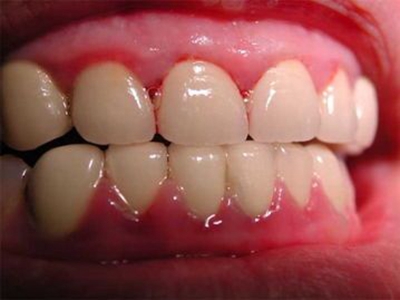

急性坏死性溃疡性龈炎,又称Vincent龈炎、梭杆菌螺旋体性龈炎、战壕口,是指发生于龈缘和龈乳头的急性炎症和坏死。本病是由多种微生物引起的机会性感染,已存在的慢性龈炎或牙周炎是患病条件,而吸烟、营养不良等可能是诱因,需要进行药物治疗。

急性坏死性溃疡性龈炎起病急,病程短,常为数天至1-2周,以龈乳头和龈缘的坏死为其特征性损害,尤以下前牙多见,初起时龈乳头充血水肿,个别龈乳头顶端可发生坏死性溃疡,上覆有灰白色坏死物,中央凹下如火山口状。龈缘如虫蚀状,坏死区出现灰褐色假膜,擦去后可见出血创面。龈乳头被破坏后与龈缘成一直线,如刀切状。病损一般不波及附着龈,患处牙龈极易出血,疼痛明显并有腐败性口臭。